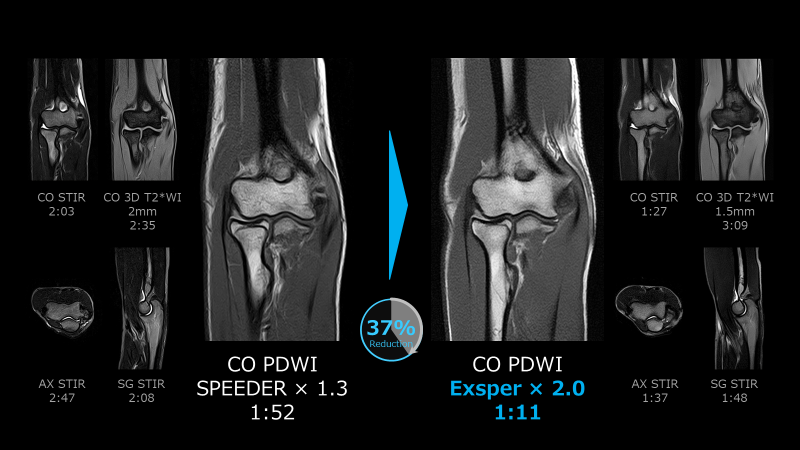

福ケ迫技師「AiCE」によるSNR向上に加え、新たに搭載された撮像時間短縮技術「Exsper」を活用することで、検査時間が予想以上に短縮されました。「Exsper」は、パラレルイメージングの一種であり、従来法の「SPEEDER」と比較して、折り返しアーチファクトが発生しにくいという特徴があります。そのため、「SPEEDER」より倍速化が容易であり、より効率的に短時間検査が可能になりました(Fig.2)。また、撮像時間の短縮に有効な圧縮センシング技術「Compress SPEEDER」も存在しますが、「Exsper」の方が画質の鮮鋭度を維持できるため、ファーストチョイスとして使用しています。その結果、1日の検査件数が約4件増加しました。そして、1日の検査をより早く終えることができるようになりました。以前は21時頃までかかっていた検査が18時頃に終えることができ、ワークライフバランスの向上にも繋がっています(Fig.3)。